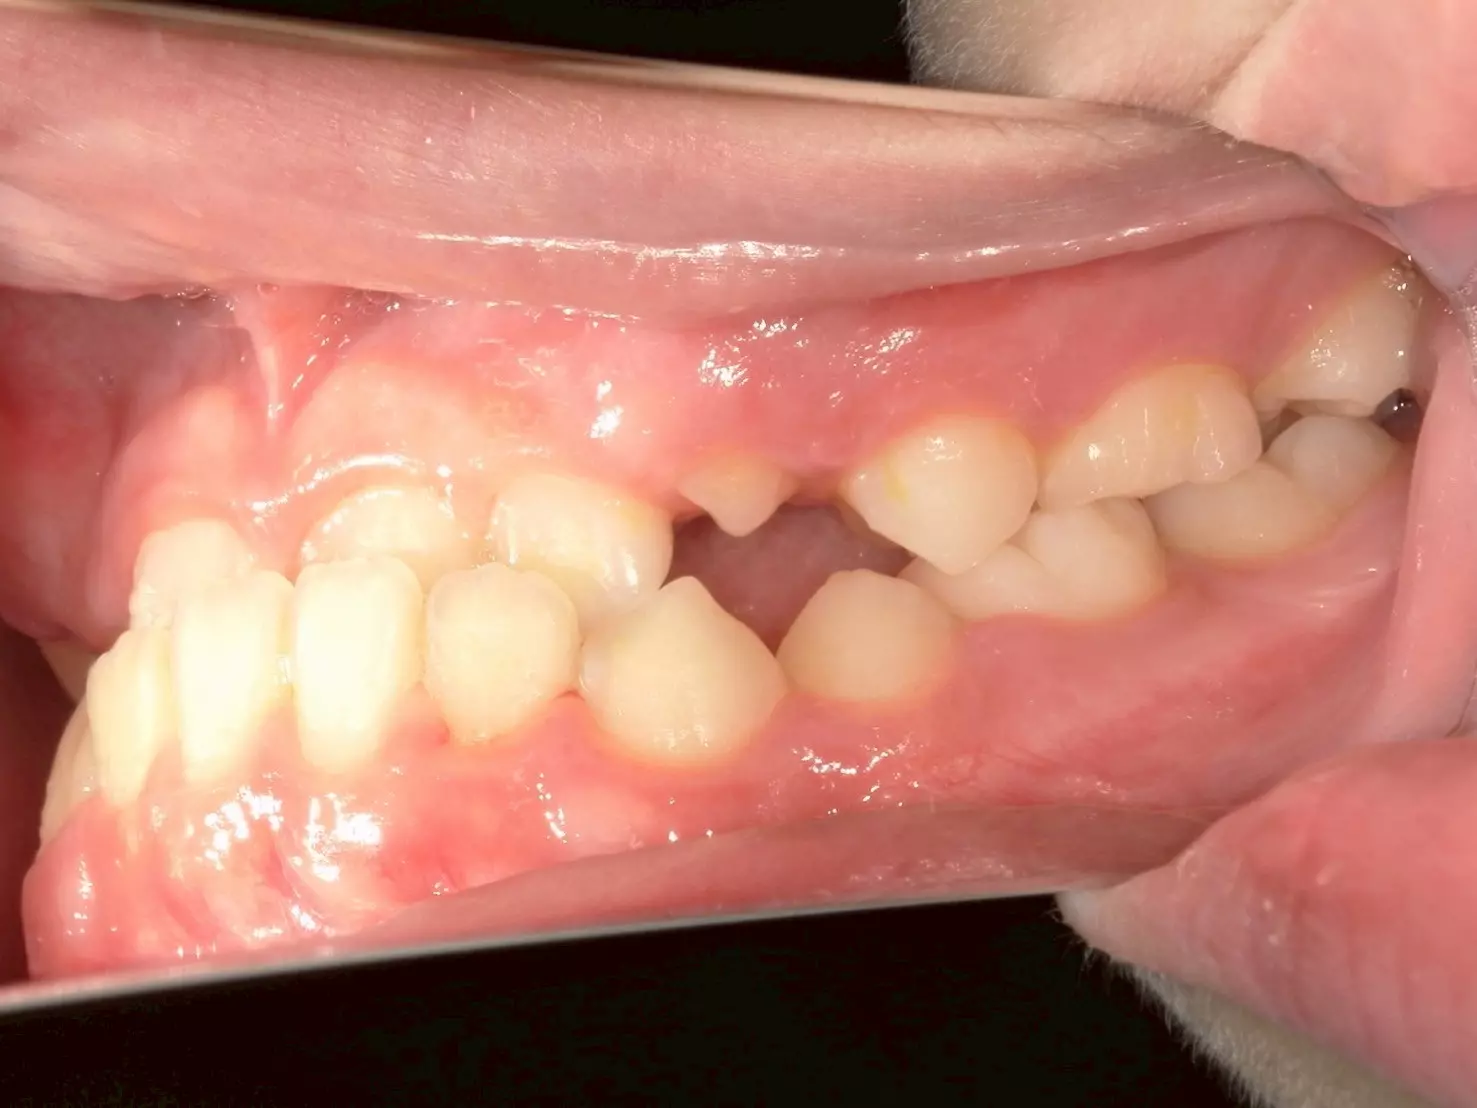

治療結束後,男孩的上顎恢復了正常生長,下顎也回到了理想位置。齒列整齊了,咬合也正常了,最重要的是他的笑容回來了!

父母告訴我們,孩子現在不僅願意開懷大笑,飲食也變得正常許多,整個人更有自信。這對一個正在成長的孩子來說,是非常寶貴的轉變。

↑治療後